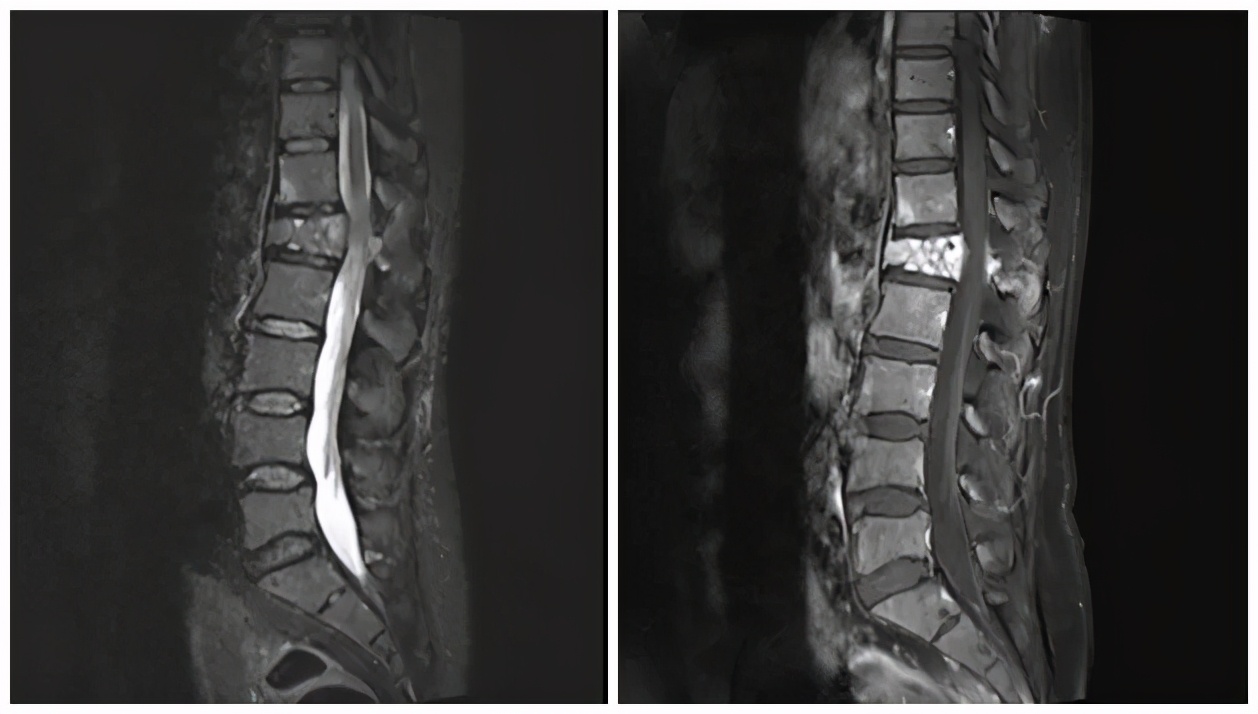

术前MR 术前MR增强